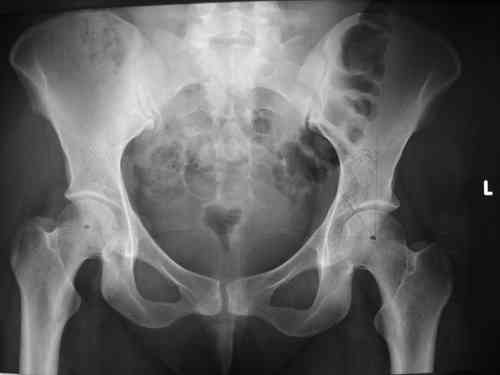

прилагаю пример с такой же давностью травмы, репонировали аппаратом

> в аппарате или одномоментно открыто. Лично я склоняюсь к аппаратному лечению на первом этапе.

задача непростая, если мало опыта в этом деле, подумайте еще раз

Маленькая иллюстрация (около 5 лет после травмы). Результат плохой - укорочение, хромота, периодически боли в спине, но больной отказывается от операции, видимо, не так все трагично.